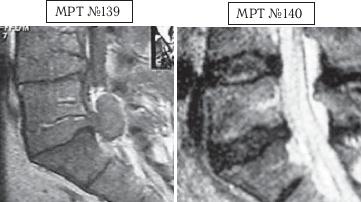

На МРТ №143 наблюдается состояние поясничного отдела позвоночника данного пациента до оперативного вмешательства: незначительных размеров грыжа межпозвонкового диска в сегменте LV-SI. Была проведена хирургическая операция межпозвонкового диска в сегменте LV-SI с целью профилактики возможных осложнений и дальнейшего прогрессирования грыжи. На МРТ №144 наблюдается состояние поясничного отдела позвоночника того же пациента после хирургического вмешательства: рецидив грыжи (но уже со значительным секвестром) межпозвонкового диска в сегменте LV-SI, стеноз позвоночного канала и, естественно, соответствующие осложнения, вызванные такой ситуацией (во избежание которых собственно и была проведена операция). На МРТ №145 наблюдается состояние поясничного отдела позвоночника того же пациента после одного курса лечения методом вертеброревитологии: отсутствие секвестрированной грыжи, стеноза позвоночного канала. |